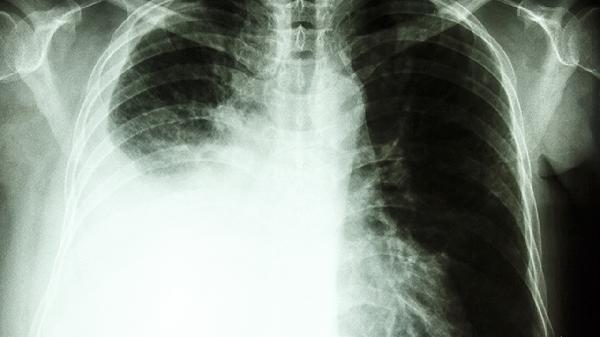

食管癌术后患者需持续监测体温、呼吸频率和血氧饱和度,出现发热、痰液黏稠或呼吸困难时应及时处理。保持病房空气流通,每日进行口腔护理。康复期可练习吹气球等肺功能锻炼,3个月内避免剧烈运动和重体力劳动。定期复查胸部CT评估肺复张情况,必要时在医生指导下使用氨溴索口服溶液等祛痰药物。